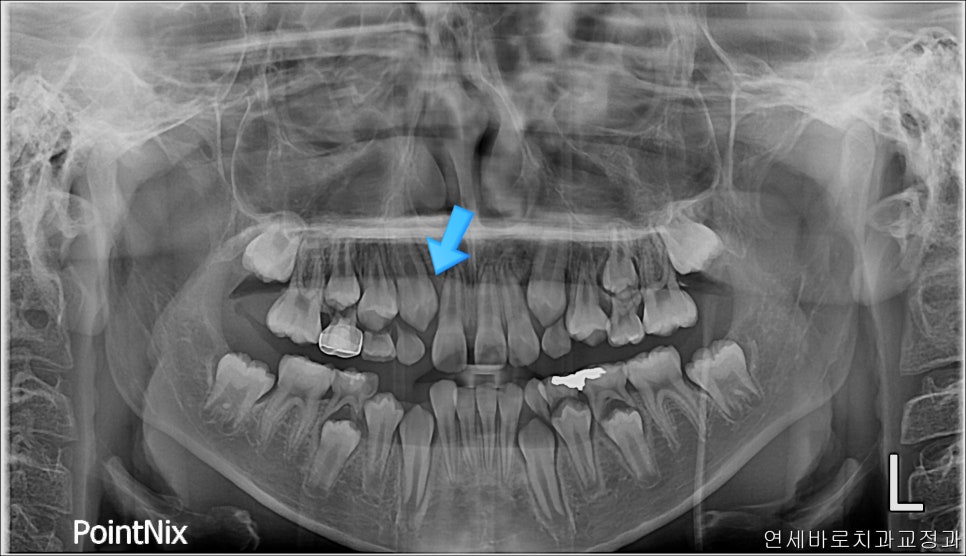

1차교정 후 2차 시작 직전의 모습입니다.

이게 무슨 교정을 한거냐 싶겠지만, 아래쪽은 일부러 남겨둔 상태이며, 위쪽 중심선을 얼굴 중심선과 일치시키며, 공간을 모두 패쇄했습니다.

화살표 치아를 발치했고, 클리피씨를 이용해 치료를 진행했습니다.